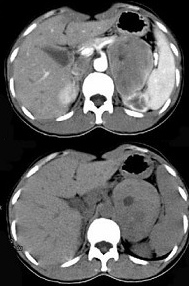

女,36岁,无任何症状,体检时超声发现左侧肾上腺区占位,CT扫描如图所示,应诊断为( )

A:左肾上腺腺瘤

B:左肾上腺囊肿

C:左肾上腺嗜铬细胞瘤

D:左肾上腺髓样脂肪瘤

E:左肾上腺转移瘤